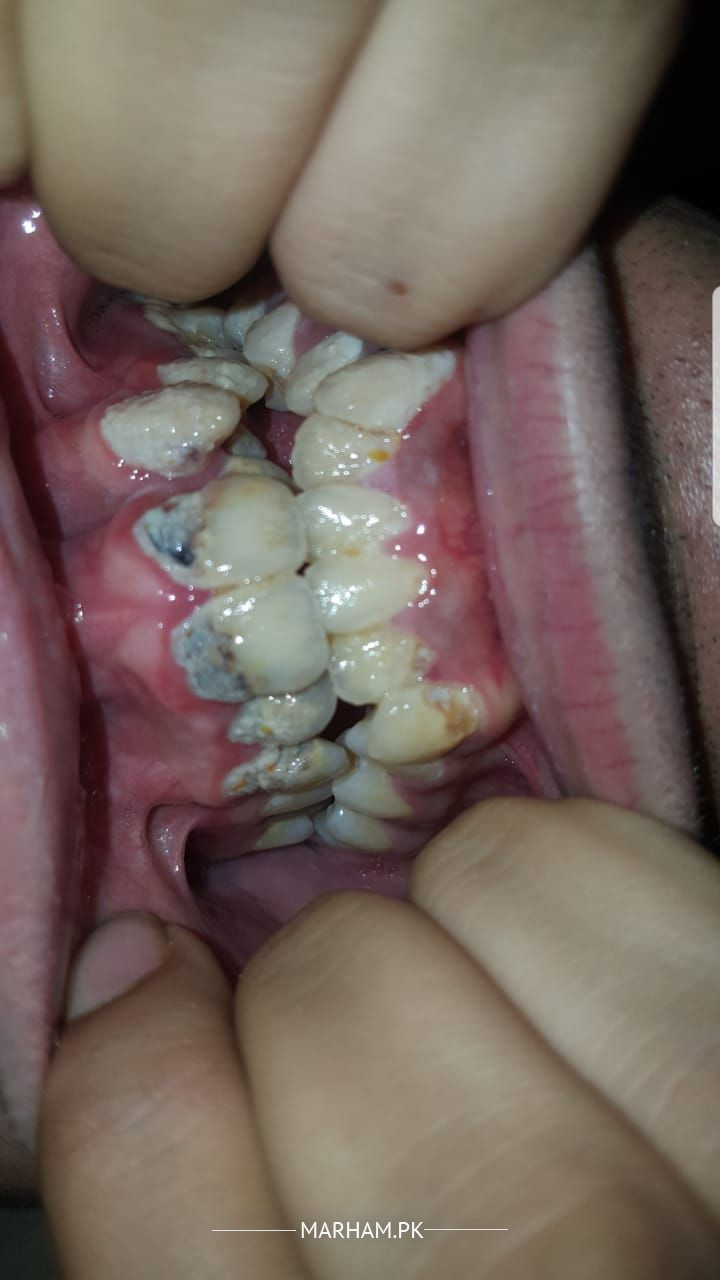

I have had teeth problems since i was a child now iam 20 and starting to lose hope if my teeth are fixable or not i have alot of cavities in my teeth and they are misaligned and are sensitive to hot and cold my lower left teeth is pretty much fully decayed so i cant eat and is very sensitive to anything please guide me for my problems thanks

There is Calculus and Carries need only SPT and Light cure Composite Filling

You need many fillings and have crooked teeth as seen in the pics. You may visit any good dentist to make a proper plan for fixing your dental problems.

you need to visit Clinic for proper treatment. u need treatment of malignant plus multiple cavities and scaling.

u feel hot n cold due to these cavities u require immediate fillings n might b root canals which could b confirmed after clinical examination n x-ray. kindly visit nearby dentist for proper treatment plan of ur teeth

your problem Is multidisciplinary ,

1. poor oral hygiene,

2. cavities needing urgent restorations alongwith

3. Orthodontic Treatment for teeth alignment and prevention of future problem.